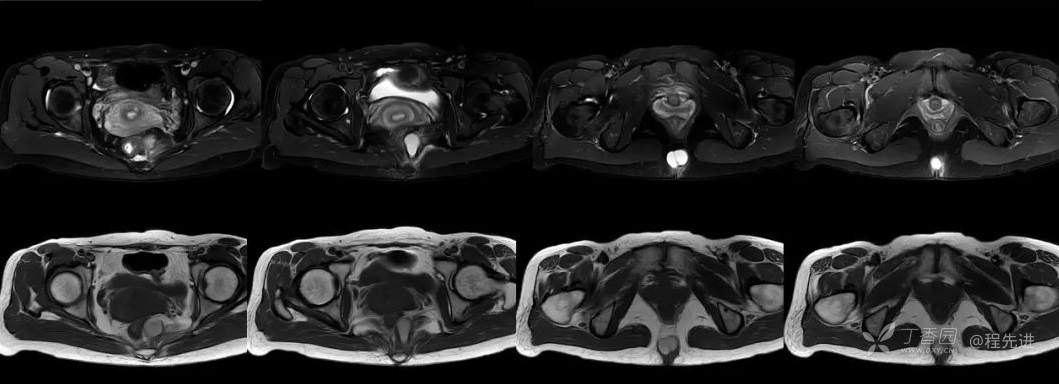

简要病史:3个月前无明显诱因出现骶尾部疼痛,胀痛为主,程度轻微,B超发现肿块3天。

体格检查:脊柱生理曲度存在,无侧弯,无压痛,活动可。尾骨尖右侧旁开2-3CM压痛。